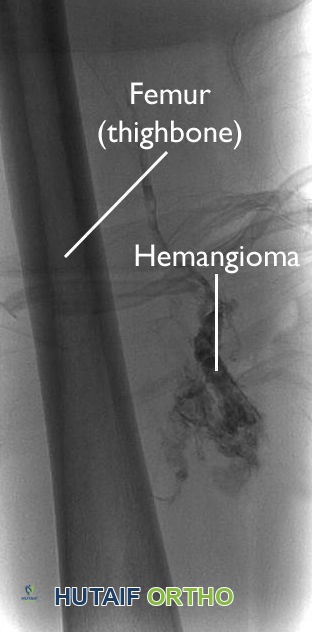

تُظهر هذه الصورة الوعائية ورماً وعائياً عميقاً في الفخذ.

تصوير الأوعية (Angiogram):

في هذا الاختبار، يتم حقن صبغة في مجرى الدم المحيط مما يجعل الورم الوعائي يظهر في صورة الأشعة السينية، مما يساعد على تحديد إمداده الدموي.